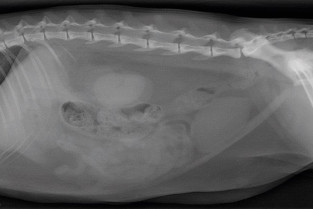

Le GEIM vous propose une séance de travaux dirigés de radiographies sur l'abdomen. Tous les aspects sont abordés sous la forme de TD de lecture de radiographies numériques.

• adopter une méthodologie pour interpréter les affections de la cavité péritonéale et rétropéritonéale chez les carnivores domestiques ;

• décrire l’aspect normal et anormal des organes péritonéaux et rétropéritonéaux chez les carnivores domestiques ;

• détecter une obstruction digestive.